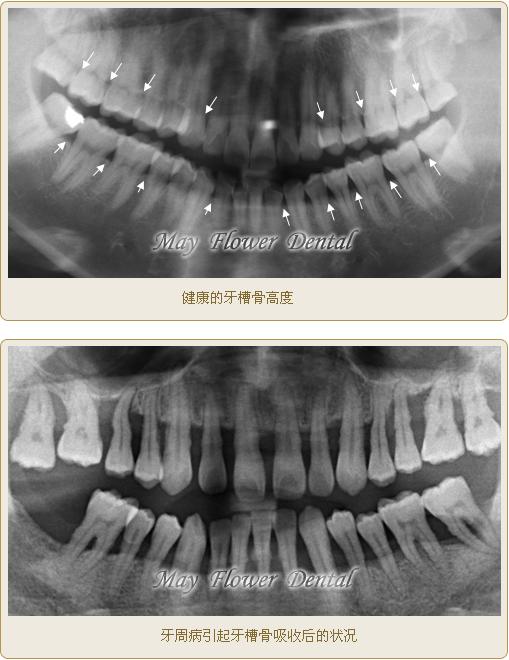

這是全口曲面斷層X光片,俗稱骷髏片,上下兩張圖片對比可以發(fā)現(xiàn)牙槽骨被吸收的情況

健康和非健康的牙齦對比